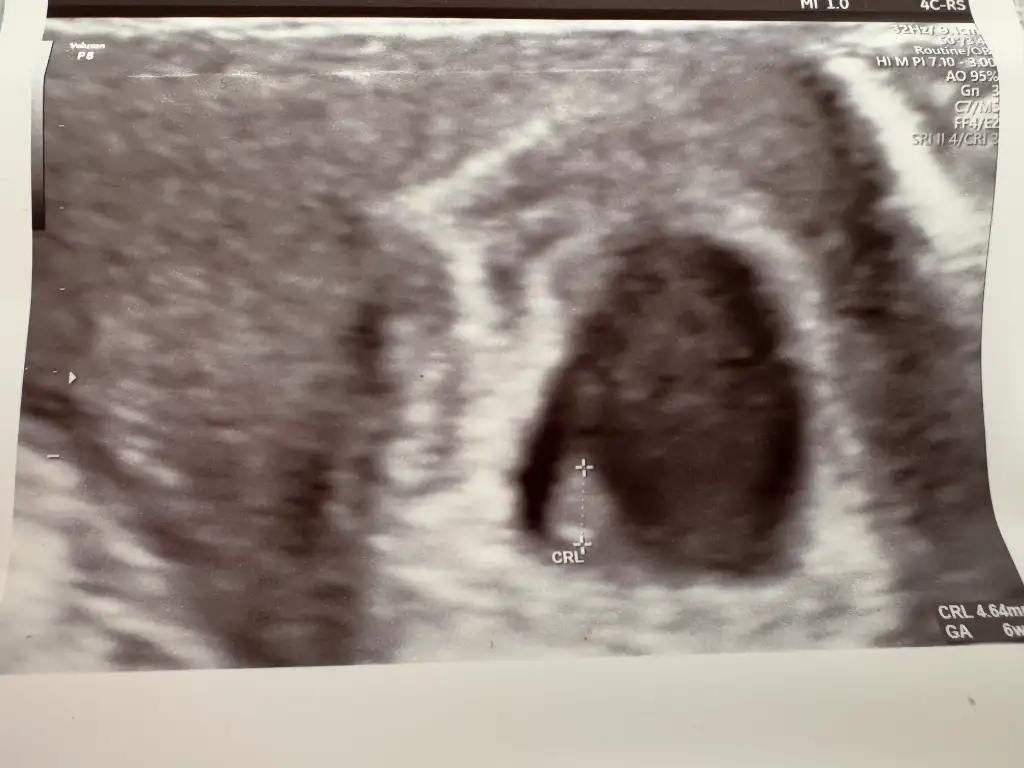

D dyquus bana da bakabilir misiniz? 6+3 haftalık abdominal